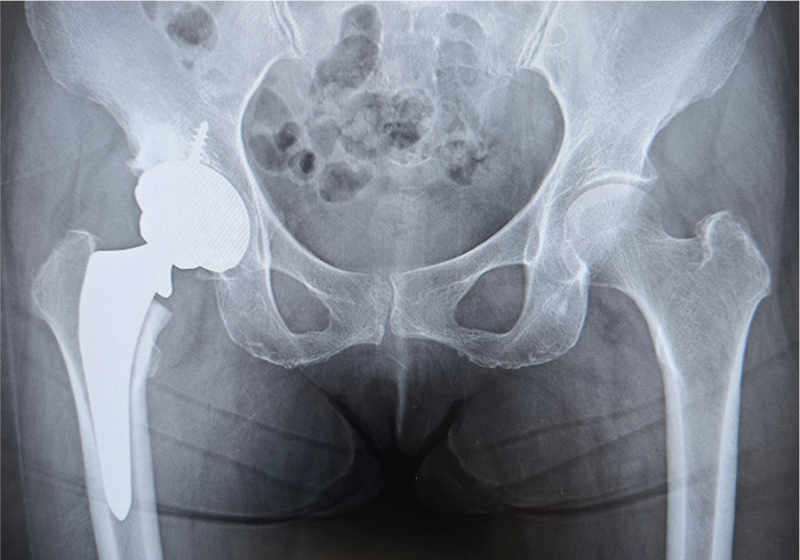

〈手術前のレントゲン〉

〈手術後のレントゲン〉(正面)

当院にて両側の人工股関節全置換術(THA)を施行。アプローチはAMIS(前方最小侵襲手術)で行い、術中に神経ブロックを併用することで、術後の疼痛コントロールを行い、術翌日から離床、リハビリを進めることができました。術後すぐに歩けることに本人も驚いていました。また、術後は一切の肢位の制限も行っていません。